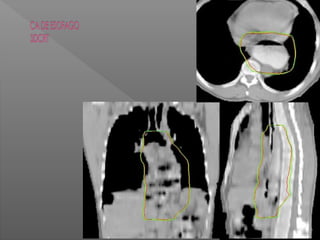

 ESOFAGO

RT preoperatoria, POP, radical

Y paliativa

Esófago cervical QT+Rt

Estadio I a III resecable

RT pop márgenes + o estrechos

Estadio I a III Inoperable QT + RT

definitiva

Estadio IV y paliativo QT+RT paliativa

Protocolo Cross y el RTOG.

CANCER DE ESOFAGO

FUSION PET CT

Int J Radiat Oncol Biol Phys. 2015 July 15; 92(4): 911–920. doi:10.1016/j.ijrobp.2015.03.030.